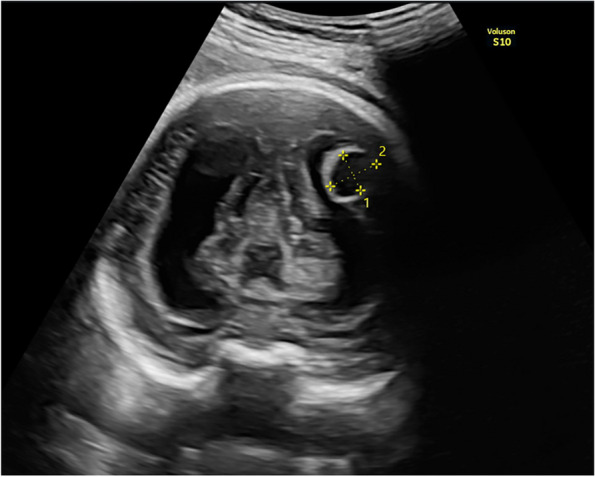

Fig. 1.

Oblique coronal scan of the posterior fetal head at 34 weeks of gestation shows well-circumscribed anechoic cyst 1 cm diameter, protruding from the left lateral wall of the lateral ventricle